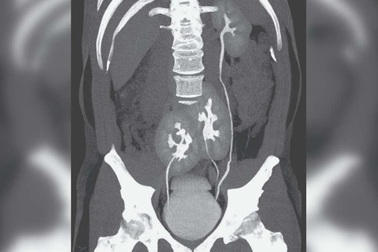

Phát hiện có tới 3… quả thận khi đi khám đau lưngBáo cáo trên Tạp chí Y học New England (NEJM), các bác sĩ khám bệnh cho một người đàn ông 38 tuổi ở Brazil cho biết đã phát hiện ra một trường hợp kỳ lạ cực kỳ hiếm gặp.